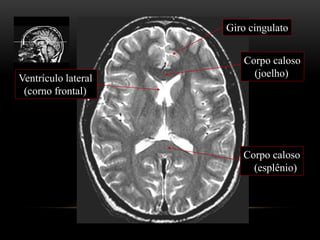

Ventrículo lateral

(corno frontal)

Corpo caloso

(joelho)

(esplênio)

Giro cingulato